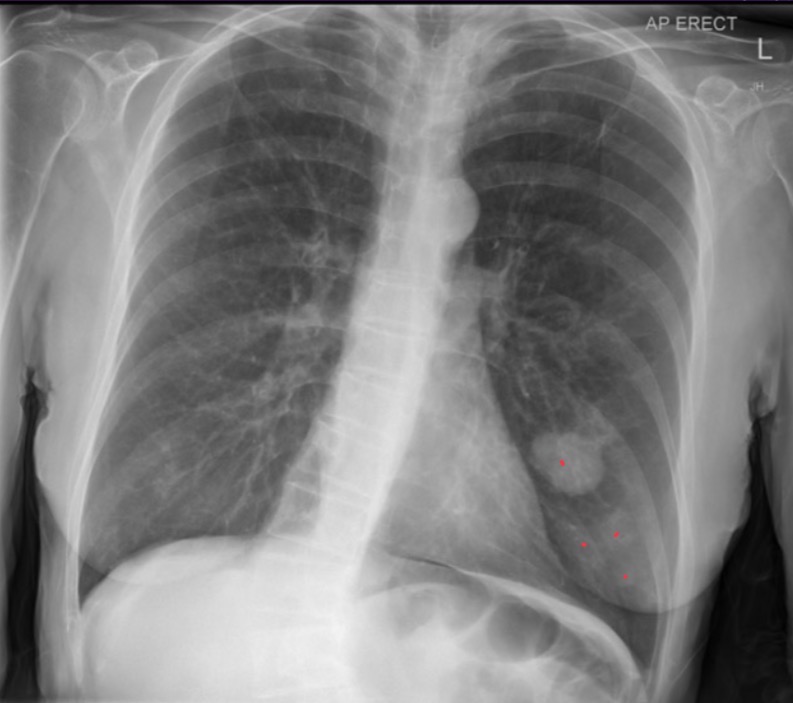

age 15, gender M, pt is acutely breathless and might have a pneumothorax. CXR nl, no consolidation collapse, pneumothorax, or effusion. Nl mediastinal contour and pulmonary vasculature

Normal chest radiograph